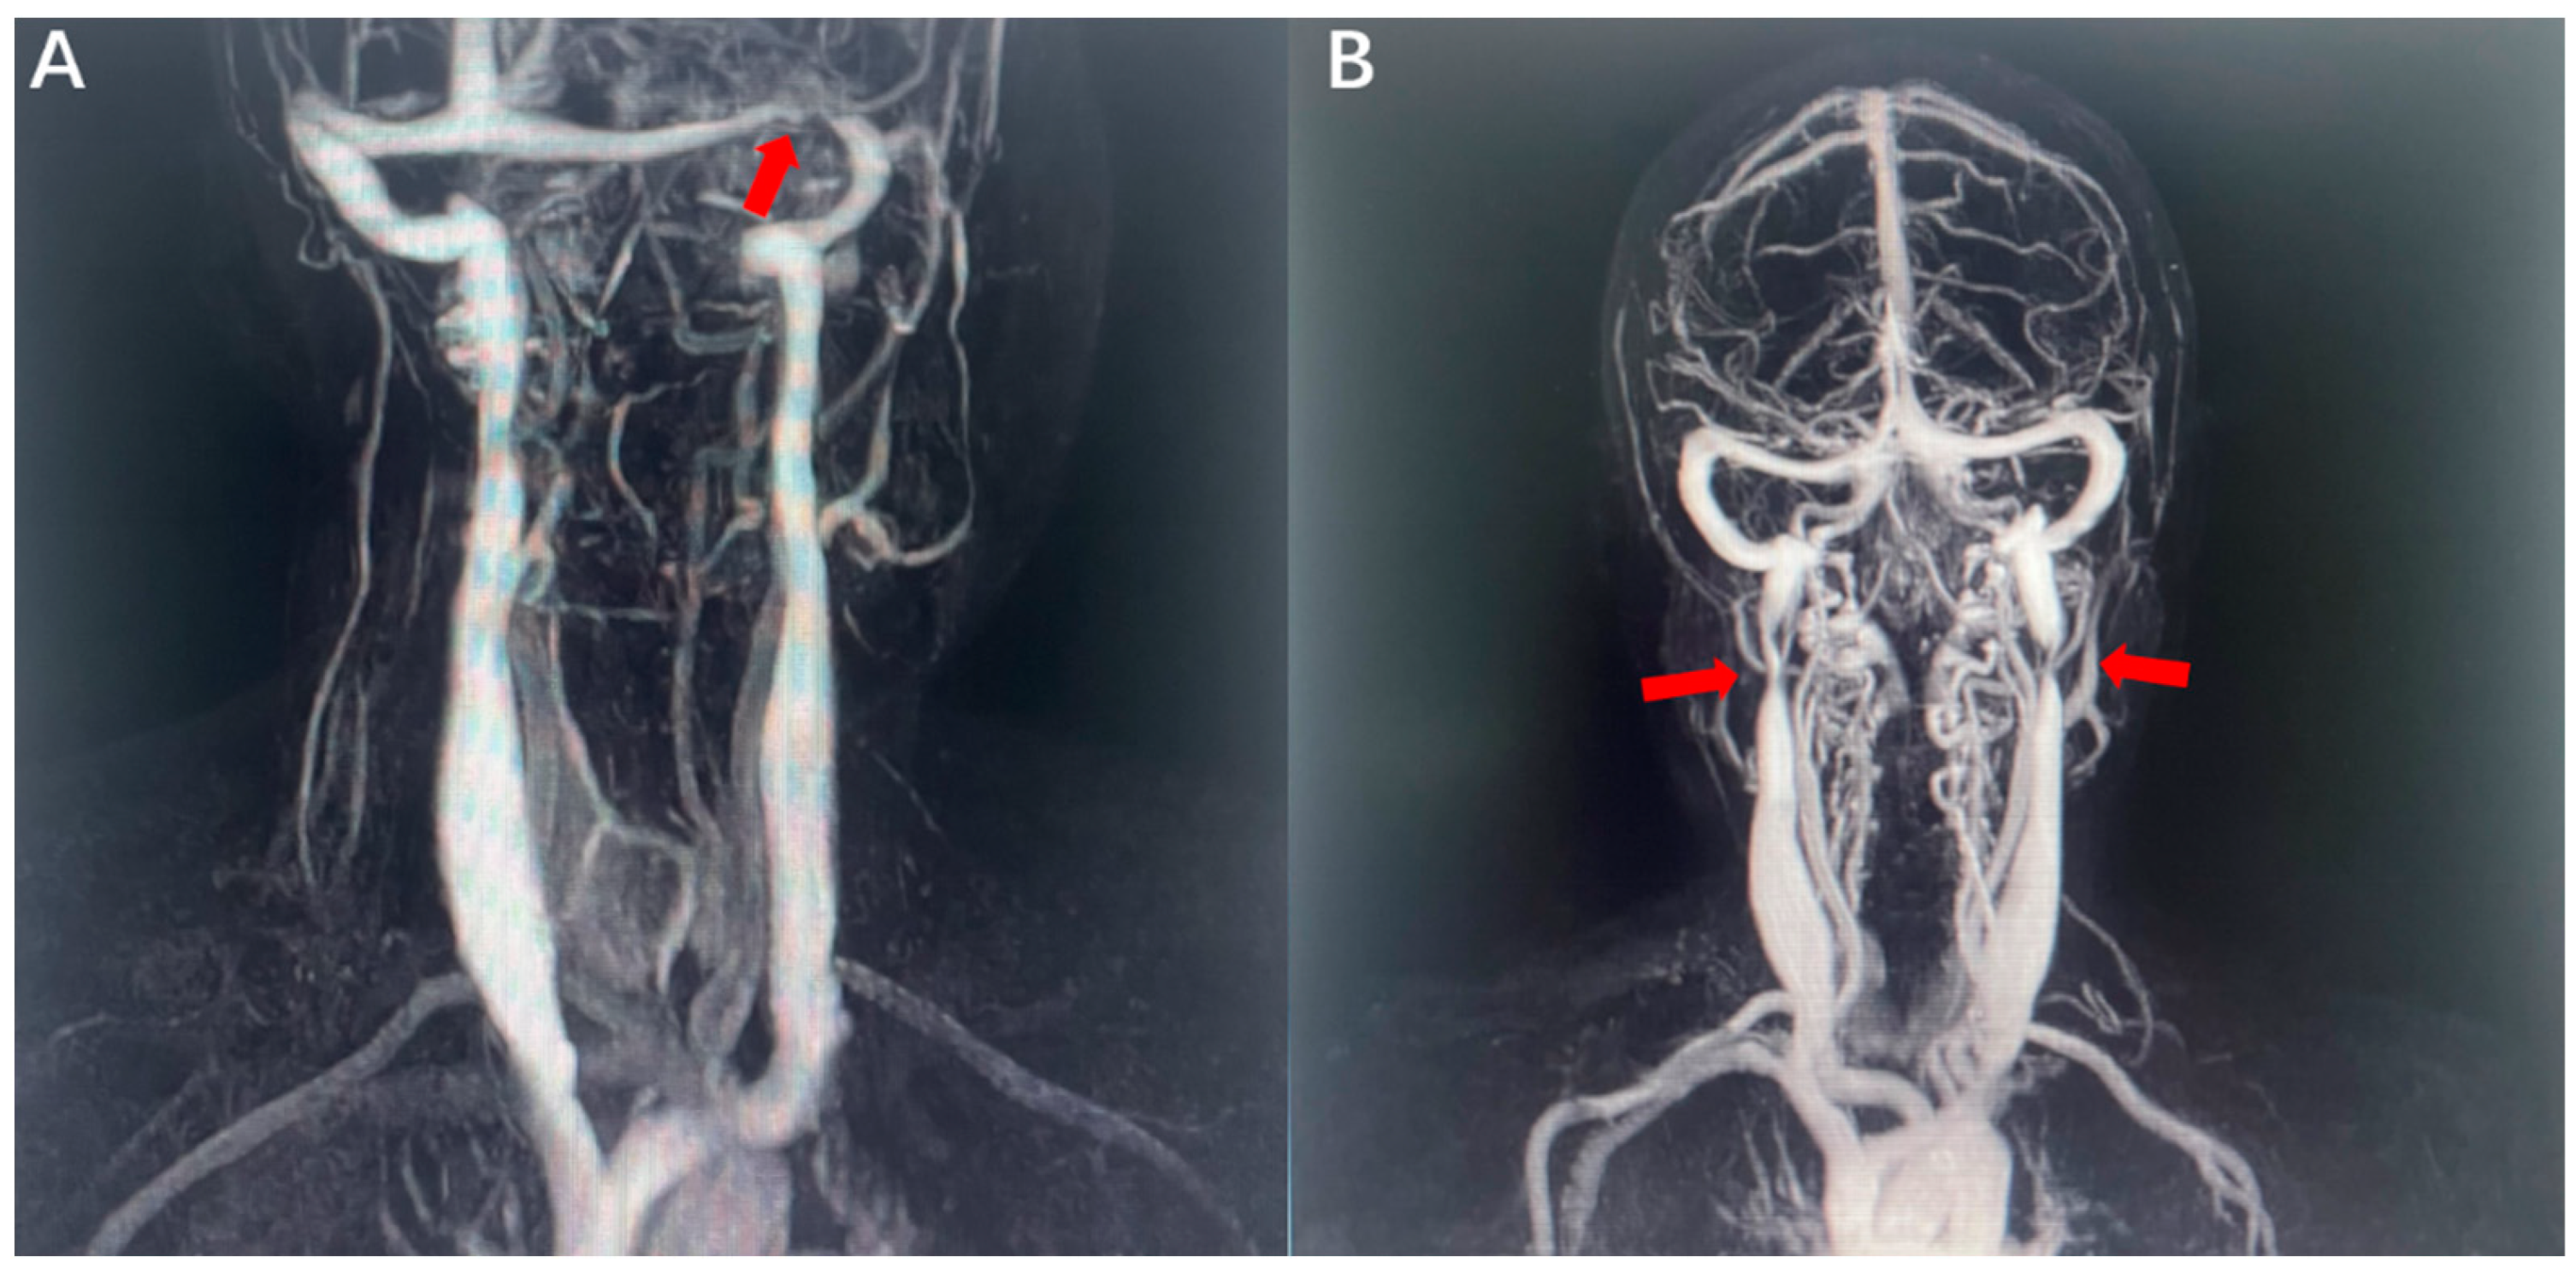

3.3. CVOD-Associated Anxiety and Depression and WMLs

4.2. CVOD-Related WMLs

4.3. Cerebral Hypoperfusion and CVOD-Associated Anxiety and Depression

4.4. Hypoperfusion and CVOD